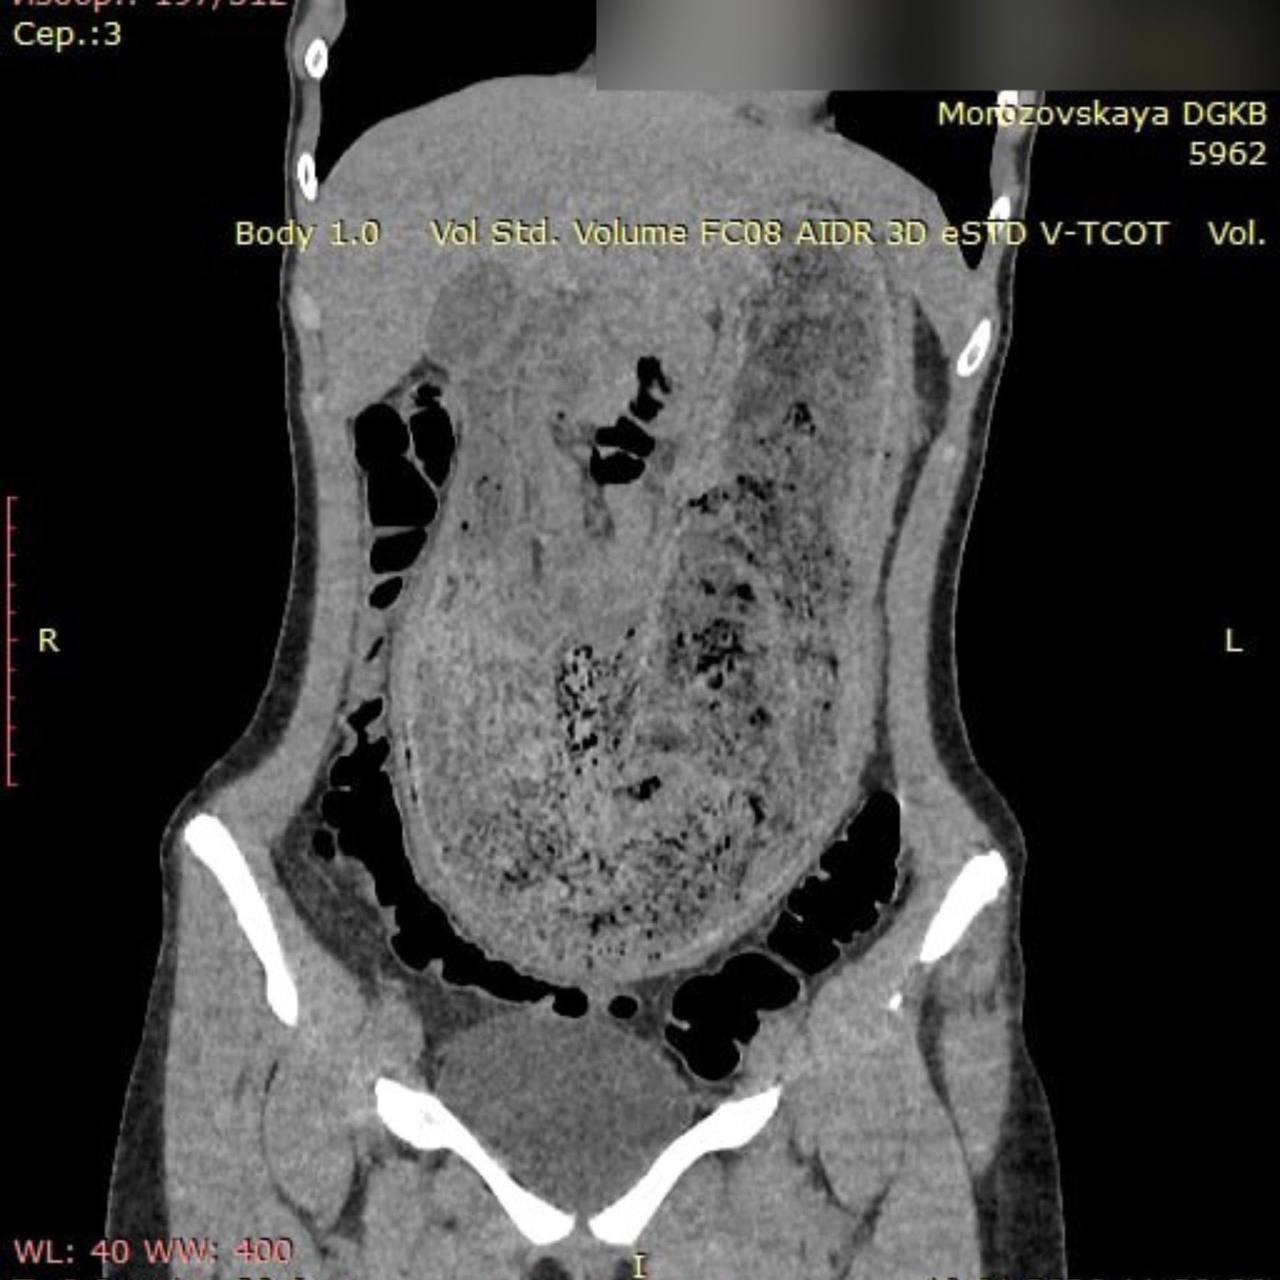

В ГБУЗ «Морозовская детская городская клиническая больница» поступила 17-летняя пациентка в крайне тяжёлом состоянии. Девушку мучили невыносимые боли в животе и постоянная рвота. В ходе обследования врачи обнаружили трихобезоар, заполнивший весь желудок и часть двенадцатиперстной кишки.

Операция по удалению волосяного комка длилась более двух часов. Как уточнили «Медицинской России», размер образования достигал 25 см в длину и 15 см в ширину.